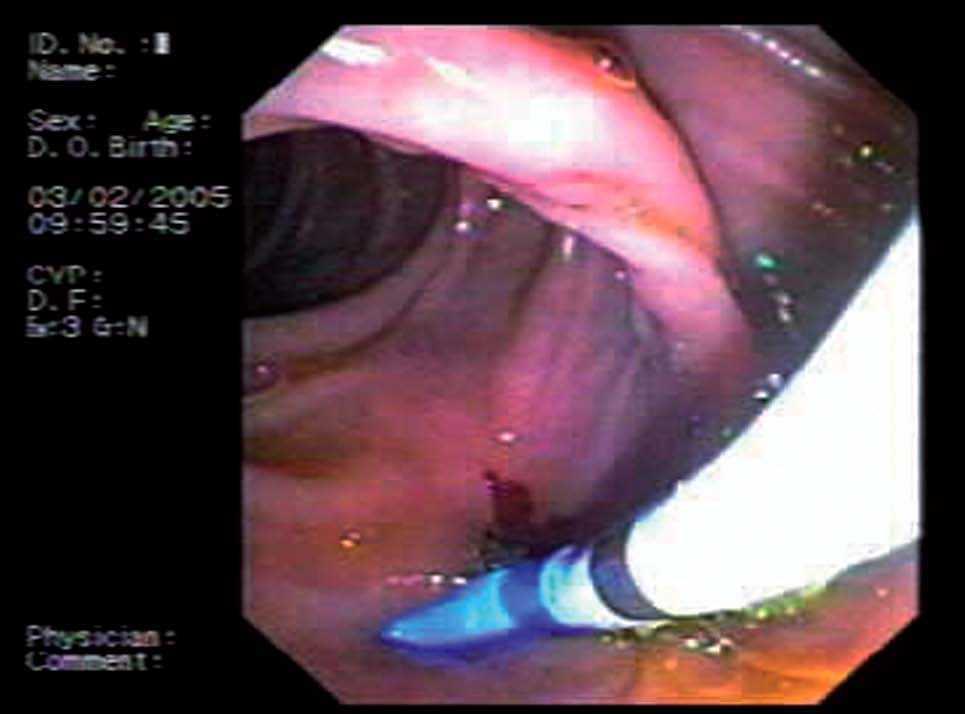

Mujer de 76 años de edad, con antecedentes personales de colecistectomía 30 años antes y de esfinterotomía endoscópica hace 10, por coledocolitiasis. Ingresa en nuestro servicio por presentar colestasis. Los datos analíticos más relevantes son: bilirrubina total 3 mg/dl (0-1,1), GGTP 892 U/l (8-61), fosfatasa alcalina 530 U/l (40-129), GOT 94 U/l (6-38) y GPT 62 U/l (6-41). Se realizan ecografía abdominal y colangio-RM que ponen de manifiesto la presencia de dilatación de las vías biliares y estenosis de la coledocoduodenostomía previa. Ante estos hallazgos, se coloca una prótesis biliar y se realiza drenaje interno-externo. Esta técnica se lleva a cabo en colaboración con el radiólogo intervencionista. En primer lugar, por vía transparietal-hepática se introduce una guía metálica hasta la ampolla de Vater. El endoscopista por vía duodenal sitúa una prótesis de plástico de 10 F y 7 cm, comprobando al terminar el buen anclaje de la misma (fig. 1). Tres días después del procedimiento la paciente refiere dolor abdominal y naúseas, por lo que se solicita nueva ecografía abdominal que demuestra que la prótesis está en el conducto hepático izquierdo. El intento de extracción mediante CPRE resulta infructuoso, por lo que finalmente la prótesis se recupera por vía transparietal-hepática (fig. 2).

Fig. 2. Extracción de prótesis migrada a conducto hepático izquierdo.